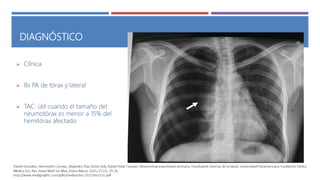

DIAGNÓSTICO

 Clínica

 Rx PA de tórax y lateral

 TAC: útil cuando el tamaño del

neumotórax es menor a 15% del

hemitórax afectado